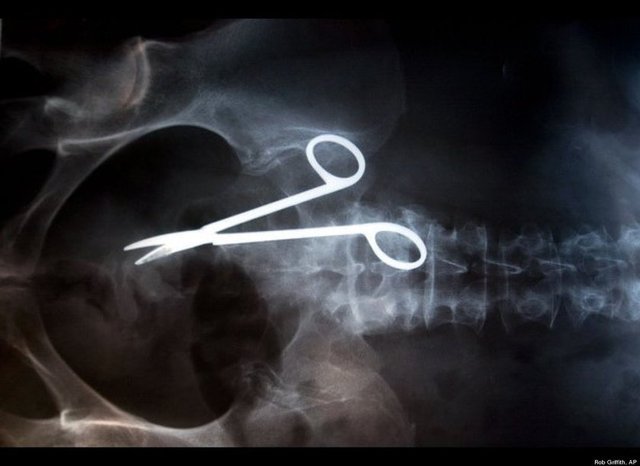

Röntgen filmlerindeki akıl almaz görüntüler

Bu görüntüler sizi çok şaşırtacak...

HABERTURK.COM / SAĞLIK SERVİSİ - Bu röntgen filmleri bildiklerinizden biraz farklı... Kiminde unutulmuş bir bıçak kiminde kablo... İşte gözlerinize inanamayacağınız o cisimler...